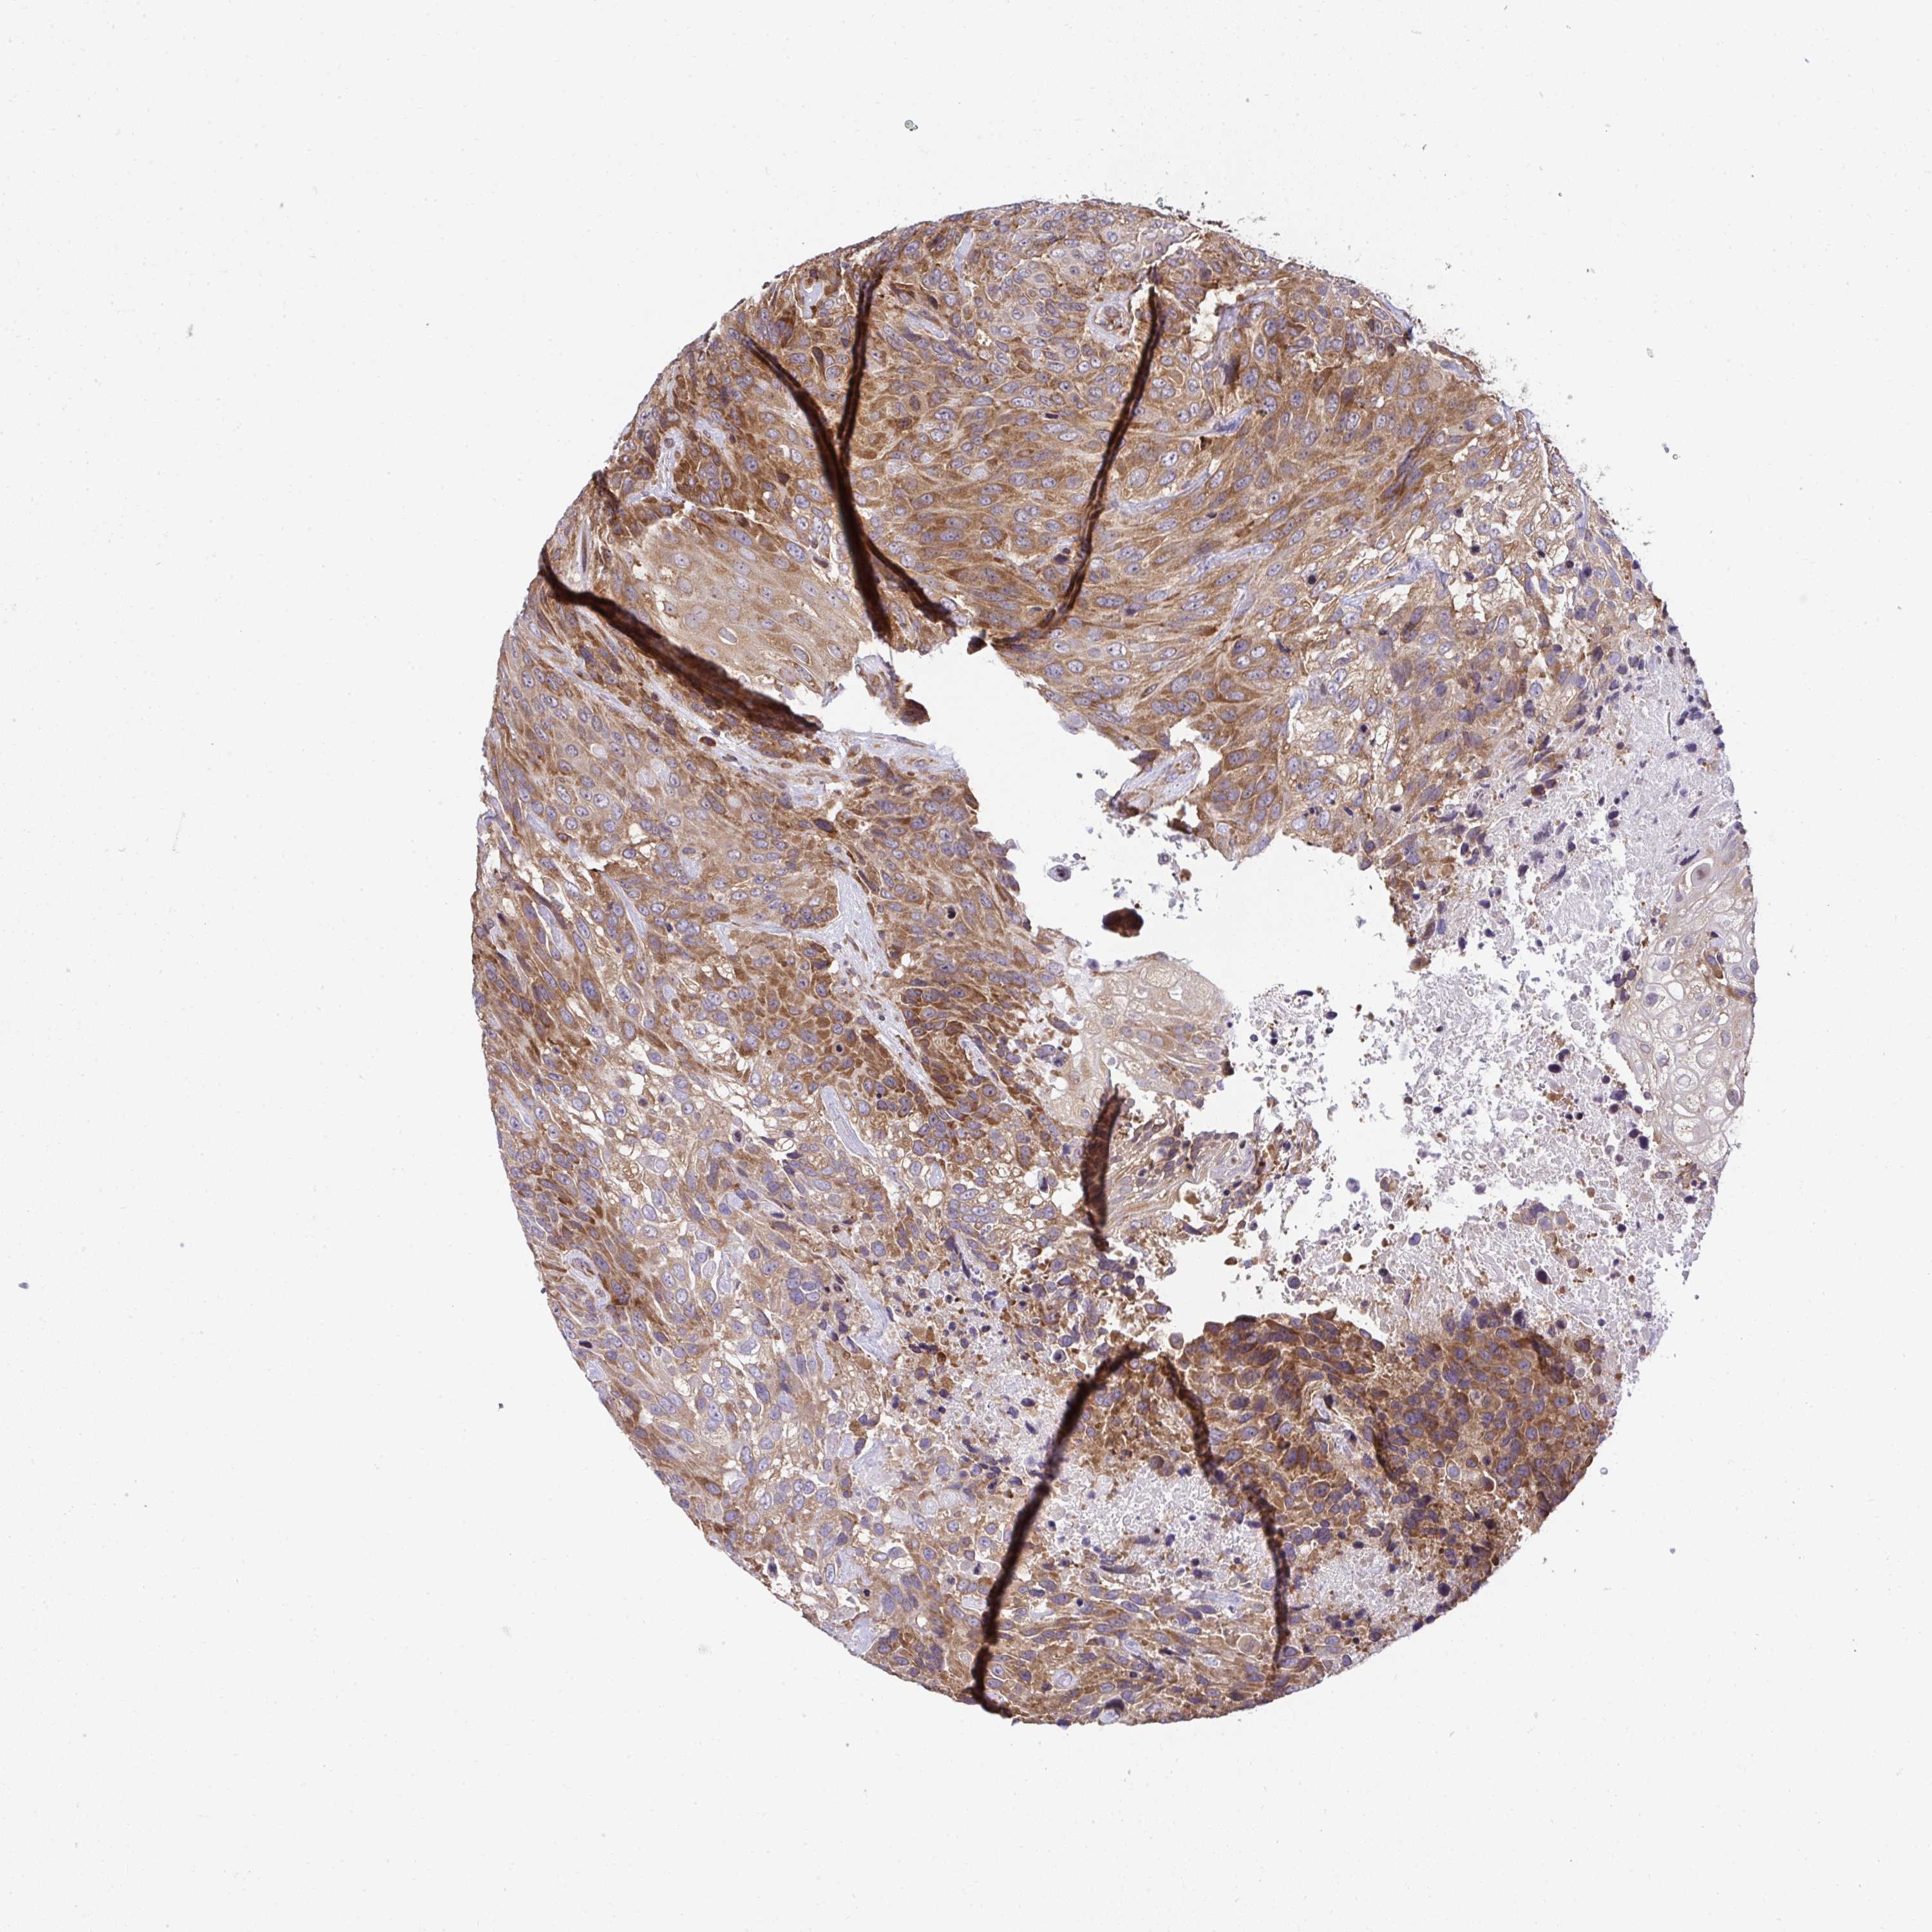

UROTHELIAL CANCER - Protein expressioni

A mouse-over function shows sample information and annotation data. Click on an image to view it in a full screen mode. Samples can be filtered based on level of antibody staining by selecting one or several of the following categories: high, medium, low and not detected. The assay and annotation is described here.

Note that samples used for immunohistochemistry by the Human Protein Atlas do not correspond to samples in the TCGA dataset.

Antibody stainingi

Antibody staining in the annotated cell types in the current human tissue is reported as not detected, low, medium, or high, based on conventional immunohistochemistry profiling in selected tissues. This score is based on the combination of the staining intensity and fraction of stained cells.

Each image is clickable and will lead to virtual microscopy that enables deeper exploration of all samples and also displays staining intensity scores, fraction scores and subcellular localization as well as patient and tissue information for each sample.

Antibody HPA056586

Staining

High

Medium

Low

Not detected

Intensity

Strong

Moderate

Weak

Negative

Quantity

>75%

75%-25%

<25%

None

Location

Nuclear

Cytoplasmic/membranous

Cytoplasmic/membranous,nuclear

Urothelial carcinoma, High grade

Urothelial carcinoma, Low grade